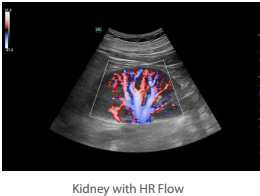

HR Flow (High Resolution Flow)

Τεχνική η οποία παρέχει αισθητά καλύτερη ποιότητα εικόνας στην PW Doppler και στην Colour Doppler απεικόνιση αυξάνοντας την ακριβή απεικόνιση των αγγείων και την ευαισθησία στην ανίχνευση της ροής αποτρέποντας την «υπερχείλιση» των αγγείων. Εφαρμόζεται σε όλες τις ηχοβόλες κεφαλές τύπου Convex, Linear, Microconvex καλύπτοντας όλο το φάσμα των διαγνωστικών εξετάσεων σε παιδιά και ενήλικες